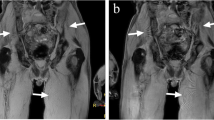

Whole-body MR examination in a 60-year-old man with newly diagnosed multiple myeloma illustrates agreement between sequences. a Coronal T1-weighted and b STIR images, and c reconstructed coronal MIP view from DWI (inverted grayscale, b = 800 s mm−2) show multiple areas of low signal typical for myeloma foci (arrows)

Whole-body MR examination in a 73-year-old man with newly diagnosed myeloma illustrates false-positive findings of the STIR and DWI sequences. a Coronal T1-weighted MR image shows a high signal intensity rounded focus typical for a vertebral hemangioma (arrow in a). b Coronal STIR image and c reconstructed coronal MIP view from DWI (inverted grayscale, b = 800 s mm−2) show rounded area of intermediate signal on STIR (arrow in b) and impeded diffusion (arrow in c) misinterpreted as a myeloma focus on both sequences